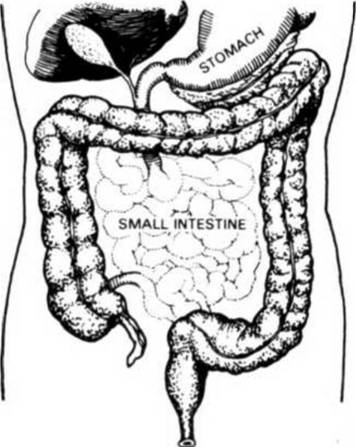

ABOVE What a person's Colon should be.

BELOW: What happens when the COLON FAILS TO RECEIVE NECESSARY COLON IRRIGATIONS.

THIS ILLUSTRATES THE LOWER PART OF THE ASCENDING COLON, SHOWING THE APPENDIX AND THE ILEOCEAL VALVE WITHIN THE JUNCTION OF THE SMALL INTESTINE WITH THE ASCENDING COLON.

The ileo - cecal valve is equipped with a safety mechanism which opens automatically to let matter pass through from the small intestine into the colon, but closes automatically to prevent any substance, liquid or solid from returning into or entering into the small intestine from the colon. If this happens, YOU'RE IN TROUBLE.

The ileo - cecal valve opens into the colon in a pouch known as the cecum which is somewhat larger than the other pouches constituting the colon. It is the first receptacle for waste residue.

The cecum does not always empty its contents into the colon immediately, and from this point onward we must, patiently and with tolerance, study this subject in some detail, whether we like it or not, as this region is one of the most vital areas controlling our indisposition, malady and infirmity on the one hand, or VIBRANT HEALTH on the other hand.